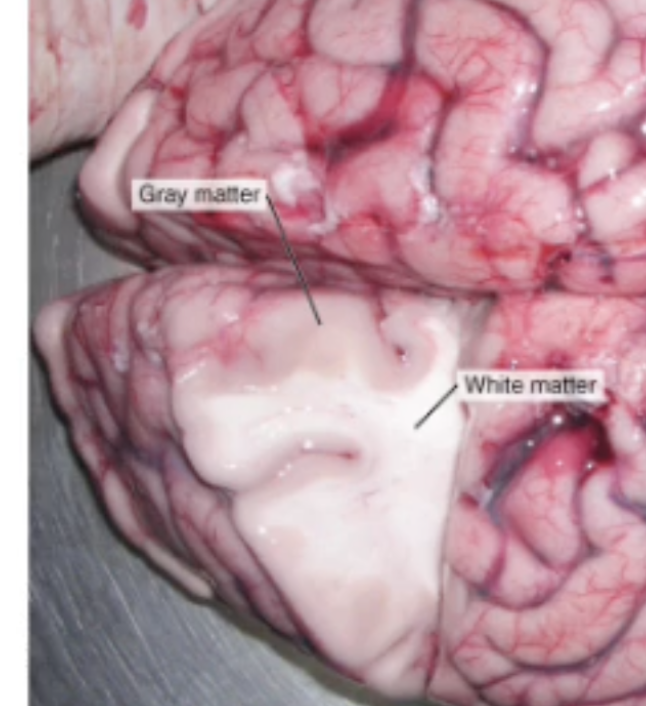

In the Spinal Cord, where is the Grey matter and White matter located

Grey matter is deep (inside), and White matter is superficial

In the CNS, what are groups of neuron cell bodies called? (Grey Matter)

Nuclei

In the CNS, what are bundles of axons called? (White Matter)

Tracts or Fibers